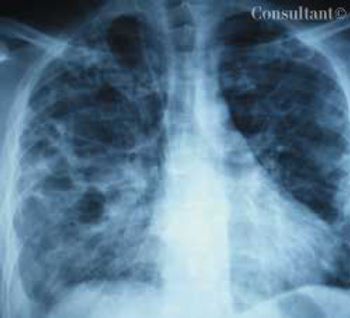

A 33-year-old man with AIDS presented to the emergency department with fever, dyspnea, cough, and pleuritic chest pain of 3 days’ duration. He had had a Pneumocystis carinii infection 3 years before recently emigrating from the Dominican Republic to the United States.